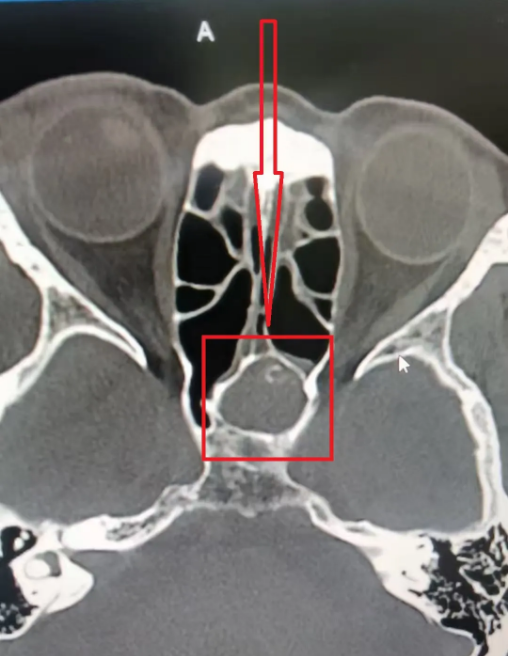

反复折腾几次之后,再次头疼难忍的她来到了徐州和平医院内科,接诊医生询问病史,进行专科查体后,考虑鼻窦炎可能,予以CT检查,结果印证了这一猜想:蝶窦腔内炎症,真菌性感染不除外,结合临床,建议林奶奶到耳鼻喉科就诊。

进一步在耳鼻喉科门诊进行检查后,最终确认为“真菌性蝶窦炎”,林奶奶的蝶窦腔内确实存在疑似真菌团块大量填充,而这,就是她头痛的罪魁祸首。

前后对比

治疗后